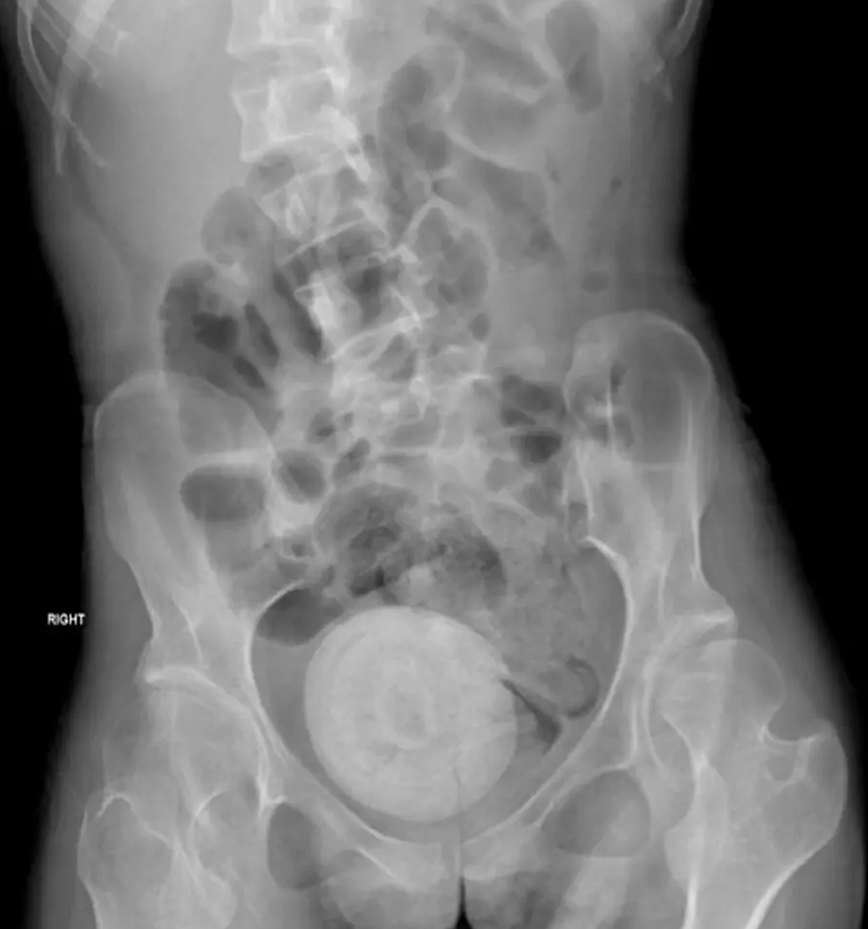

Τα συμπτώματα παρατηρήθηκαν τρεις ημέρες πριν η ασθενής μεταφερθεί εσπευσμένα στη ΜΕΘ. Είχε πυρετό, ρίγη, εμετούς, πόνους στην κοιλιά και μειωμένη όρεξη. Η αξονική τομογραφία σε λεκάνη και στην κοιλιά αποκάλυψε τον λόγο.

Το μέγεθος ήταν τόσο μεγάλο που πίεζε την ουροδόχο κύστη της γυναίκας, κάτι που οδήγησε σε ακόμη μεγαλύτερη διαρροή ούρων. Γιατροί από το Πανεπιστήμιο του Λιβάνου στη Βηρυτό διέλυσαν τον σχηματισμό της πέτρας με θεραπεία λέιζερ μέσω κρουστικών κυμάτων υπερήχων από μια συσκευή που τοποθετήθηκε στην κοιλιά της γυναίκας.